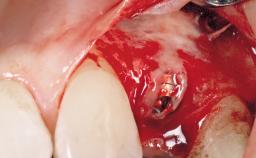

A 36-year-old female patient was referred for the replacement of the upper left central incisor (tooth 21), which had fractured. Although the tooth had been asymptomatic for many years, the crown began to loosen, at which time she presented to her dentist for an assessment. Teeth 21 and 22 had both been endodontically treated many years previously. She was a healthy individual and a non-smoker.

The crown of tooth 21 was splinted to the adjacent teeth with composite resin, and the gingiva was inflamed.